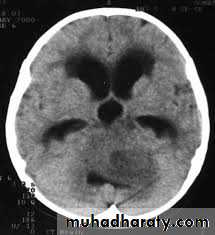

Hydrocephalous

2 types

Obstructive ( non – communicating )

Non –obstructive ( communicating )

No obstruction of the ventricular pathway , but the absorption of the csf at the level of arachnoids' granulation is occluded secondary to lodge by blood clot or inflammatory cell or infection post meningitis most commonly to occur post SAH .